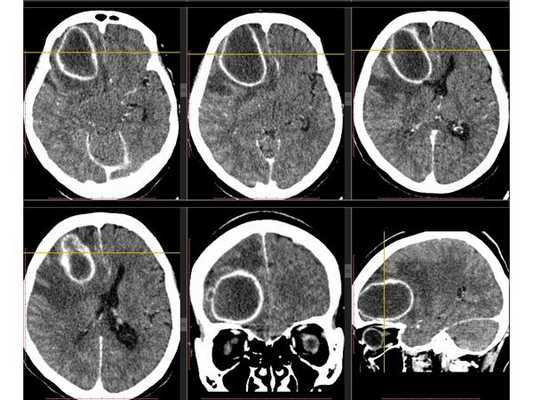

3D-реконструкция объёмного образования правой лобной доли головного мозга, выполненная на основании сканов КТ с контрастным усилением

На основании диагноза проведена краниотомия (трепанация черепа) и удаление абсцесса правой лобной доли: ⠀• выполнен дугообразный разрез мягких тканей в правой лобно-височной области; ⠀• наложено фрезевое отверстие у основания скулового отростка лобной кости, из которого краниотомом выпилен костный лоскут 6*5 см; ⠀• для остановки кровотечения использован хирургический воск и электрокоагуляция по ходу доступа; ⠀• произведено подковообразное вскрытие твёрдой мозговой оболочки основанием к сагиттальному синусу: абсцесс был хорошо отграничен капсулой и подпаянной к коре головного мозга твёрдой мозговой оболочкой; ⠀• тонким шпателем твёрдая мозговая оболочка постепенно отделена от коры, абсцесс вскрыт — получен гной, внешне напоминающий сливки, с гнилостным запахом; ⠀• аспирировано (удалено) около 60 мл гноя; ⠀• полость абсцесса многократно промыта водными растворами перекиси водорода и фурацилина, мозг запал, имеется хорошая пульсация; ⠀• твёрдая мозговая оболочка ушита, по периметру подшито трепанационное окно, костный лоскут уложен на место, на рану наложены послойные швы и асептическая повязка. При оперативных вмешательствах по поводу абсцесса головного мозга принято оставлять дренаж в полости абсцесса. Однако, с учётом наличия хорошо сформированной капсулы, которая была визуализирована после промывания полости антисептическими растворами, принято решение не оставлять дренаж.